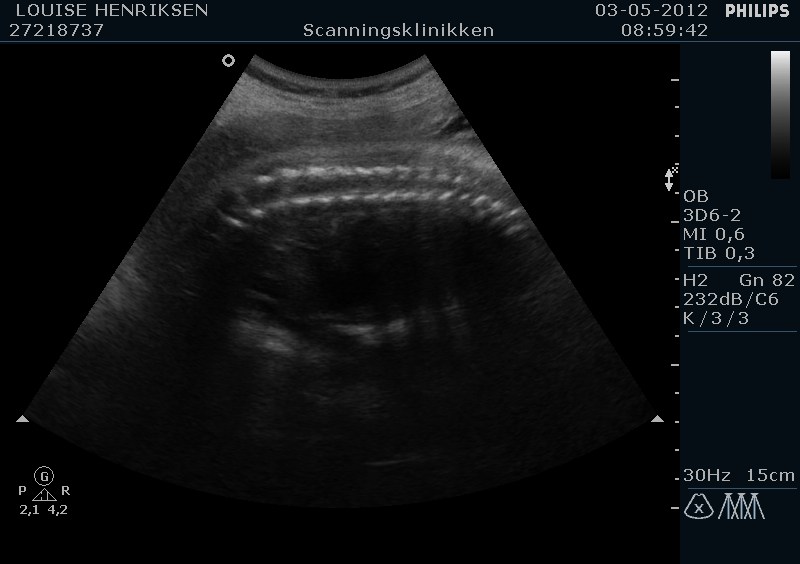

I dag skulle manden overraskes med en 4 d scanning.... og hans far var også med det var også en overraskelse, samt den lille prins....han fik bind for øjene og vi kørte mod scanning klinikken.... vi fik nogle gode sekvenser af bettemanden.. men han fylder en del derinde nu, så billederne blev ikke voldsomt gode.. men nogle fik vi dag...jeg skulle i morgen være 32 fulde uger.. mne scanningen i dag vidste34+4 dage yiarks.... jeg skal til at være færdig med den bachelor..... han vejede efter målene 1871 gram.....

så han var en fin basse...